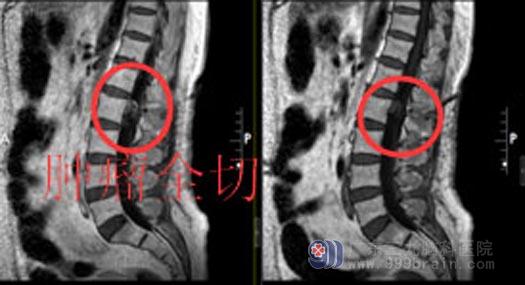

此次手术的重点和难点都在于:充分暴露硬脊膜,小心保护好马尾神经及神经根,严密缝合硬膜,防止脑脊液漏。积极地术前准备后,外五科医生团队在全麻下为陈阿姨实施“经腰2左侧半椎体入路行腰2椎水平椎管内偏左侧神经鞘瘤切除术+硬脑膜修补+腰2半椎体固定术”,术中冰冻考虑神经鞘瘤,肿瘤侵犯硬脊膜,缝合硬脊膜后无脑脊液漏,肿瘤全切,神经保护良好,固定腰2椎椎体后,手术顺利结束。

术后第一天复查腰部CT未见明显出血;术后三天复查腰椎MR显示:原占位性病变全切;病理结果示:椎管内神经鞘瘤。陈阿姨神志清楚,生命体征平稳,无头晕头痛等不适,对答流利,四肢肌力V级,感觉、肌张力正常。肿瘤全切,未出现任何后遗症,家人非常满意此次手术效果。

▲手术后